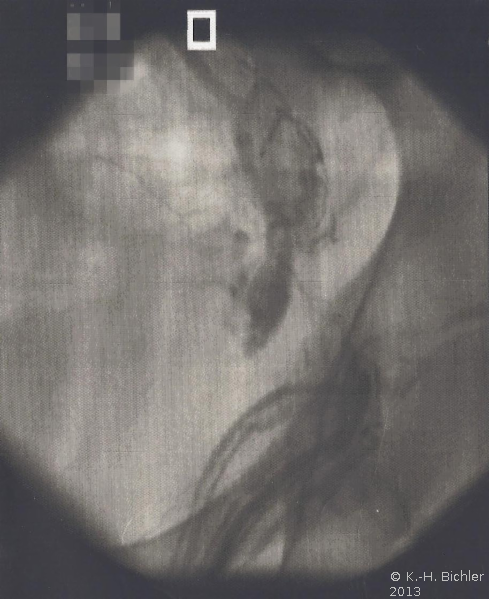

Phlebographie über eine Vene des Plexus pampiniformis. Nach Injektion von Kontrastmittel Darstellung mehrerer Kollateralen im Bereich der Beckengefäße, unter anderem zur Vena illiaca. Eine Sklerosierung wurde in Anbetracht der Kollateralen nicht durchgeführt (Abbildung HG1).